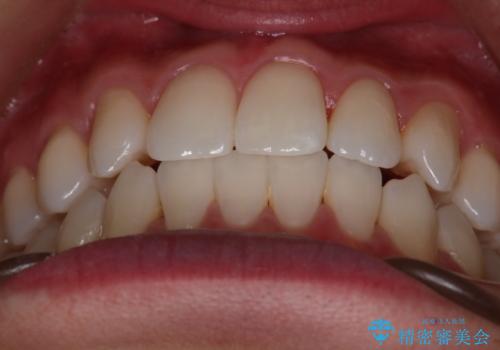

- 右上2番が欠損しており、歯並びをバランスよくしたいということで来院されました。

ワイヤー装置とマウスピースで悩まれていましたが、マウスピースで治療可能と判断致しましたのでマウスピースにて治療しました。

IPR、歯列弓拡大、ゴム掛けを行い歯並びを整える治療計画を立てました。

右上2番が欠損しているため、見た目と噛み合わせの両方のバランスを整えるために経過を追いながら必要な部位にゴム掛けをしました。

最終的に、見た目も噛み合わせも患者様に満足いただけました。